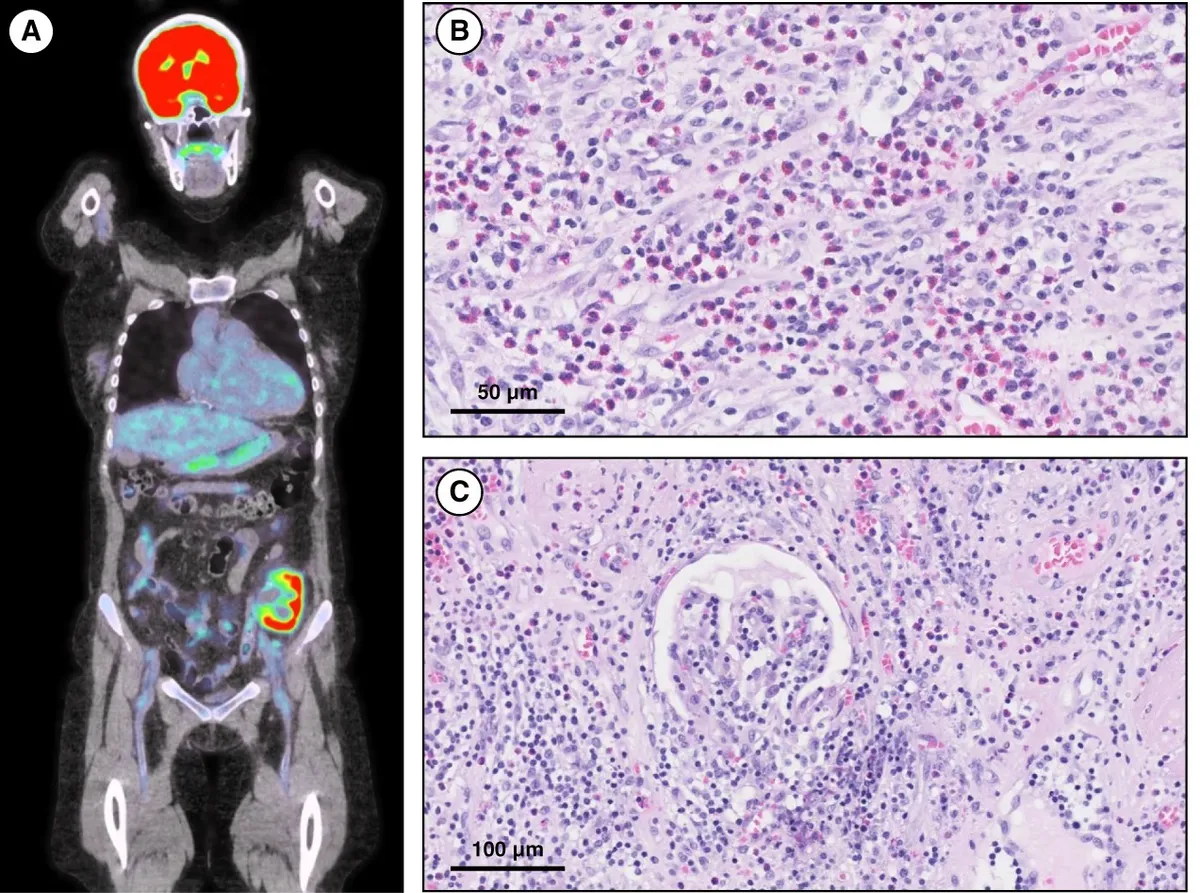

Rejeição de enxerto e eosinofilia!

Rejeição de enxerto e eosinofilia!Descubra como a hipereosinofilia pode revelar rejeição mediada por anticorpos em uma paciente transplantada renal após falência do enxerto. Um caso que destaca o papel dos eosinófilos no diagnóstico diferencial e manejo clínico!

Valkercyo Feitosa

2 anos atrás